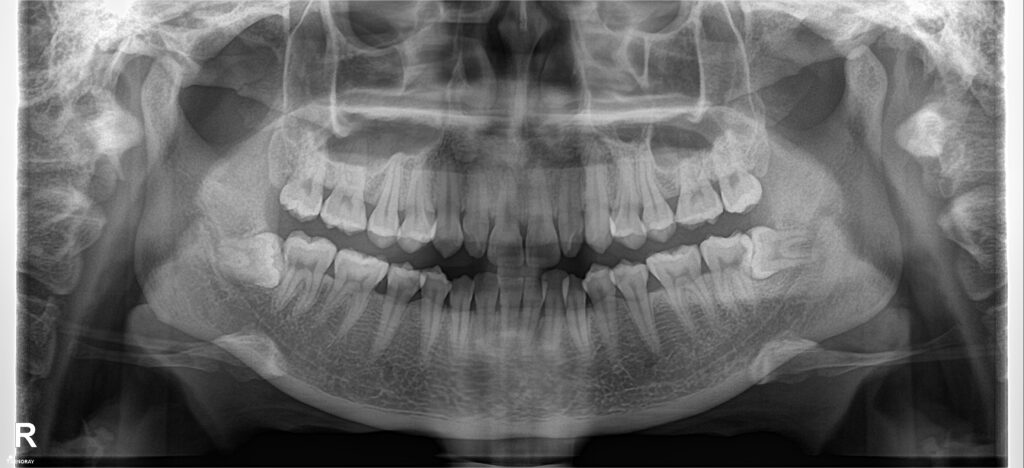

Bệnh nhân có cung hàm vuông, răng chen chúc cả hai hàm, khuôn miệng cười không đẹp. Gắn mắc cài kim loại truyển thống, sử dụng dây cung nong Damon qua các giai đoạn theo trình tự: San bằng, sắp đều, xử lí thiếu khoảng, đóng khớp cắn & tinh chỉnh, tháo niềng.